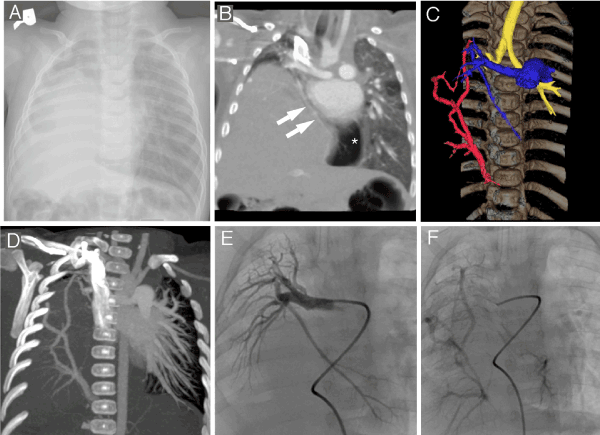

5-month-old male was referred to tertiary healthcare institution for poor weight gain, suspected cardiac anomalies and propensity to lung infections. Chest X-ray revealed right diaphragmatic hernia and malposition of the heart to the right side of the chest (Figure 1A). Blood test ruled out bacterial infection. Echocardiographic findings were consistent with subaortic ventricular septal defect, slight aortic dextraposition and pronounced pulmonary hypertension. Chest CT showed marked elevation of the right hemidiaphragm, most of the right hemithorax was occupied by the liver, no right lung atelectasis (Figure 1B). Abnormal right bronchial tree was detected with abrupt ending of the right upper and middle lobe bronchi. Right pulmonary artery was hypoplastic and supplied the right lower lobe, two right pulmonary veins entered liver tissue and coursed through liver parenchyma caudally to enter portal vein (Figures 1B, 1C and 1D). Smooth right border of the left atrium also was consistent with anomalous right pulmonary venous drainage. In addition, one of the right pulmonary artery branches was noticed to descend and traverse mediastinum to the left hemithorax, were hyperinflated parenchyma of the herniated right lung was observed (Figure 1B). Arterial phase of selective angiography showed filling of the hypoplastic right pulmonary artery with one of the branches traversing middle line of the body to the left hemithorax (Figure 1E), pulmonary venous phase was consistent with CT findings and depicted downward flow of contrast medium towards hepatic hilum (Figure 1F).

Figure 1.

A - frontal chest x-ray showing opaque right hemithorax

B - CT frontal maximum intensity projection reconstruction showing branch of the right pulmonary artery (two arrows) traversing mediastinum to supply the part of the right lung dislocated leftwards to left hemithorax (dislocated lung is of lower attenuation compared to left lung most probably because of hyperinflation - asterisk)

C - colored volume rendering image showing hypoplastic right pulmonary artery (blue), right pulmonary veins descending towards portal vein (red) and short trachea with high positioned carina (yellow)

D - maximum intensity projection showing right pulmonary vein drainage pattern

E - arterial phase of selective angiography showing right pulmonary artery

F - pulmonary venous phase of selective angiography showing right pulmonary veins